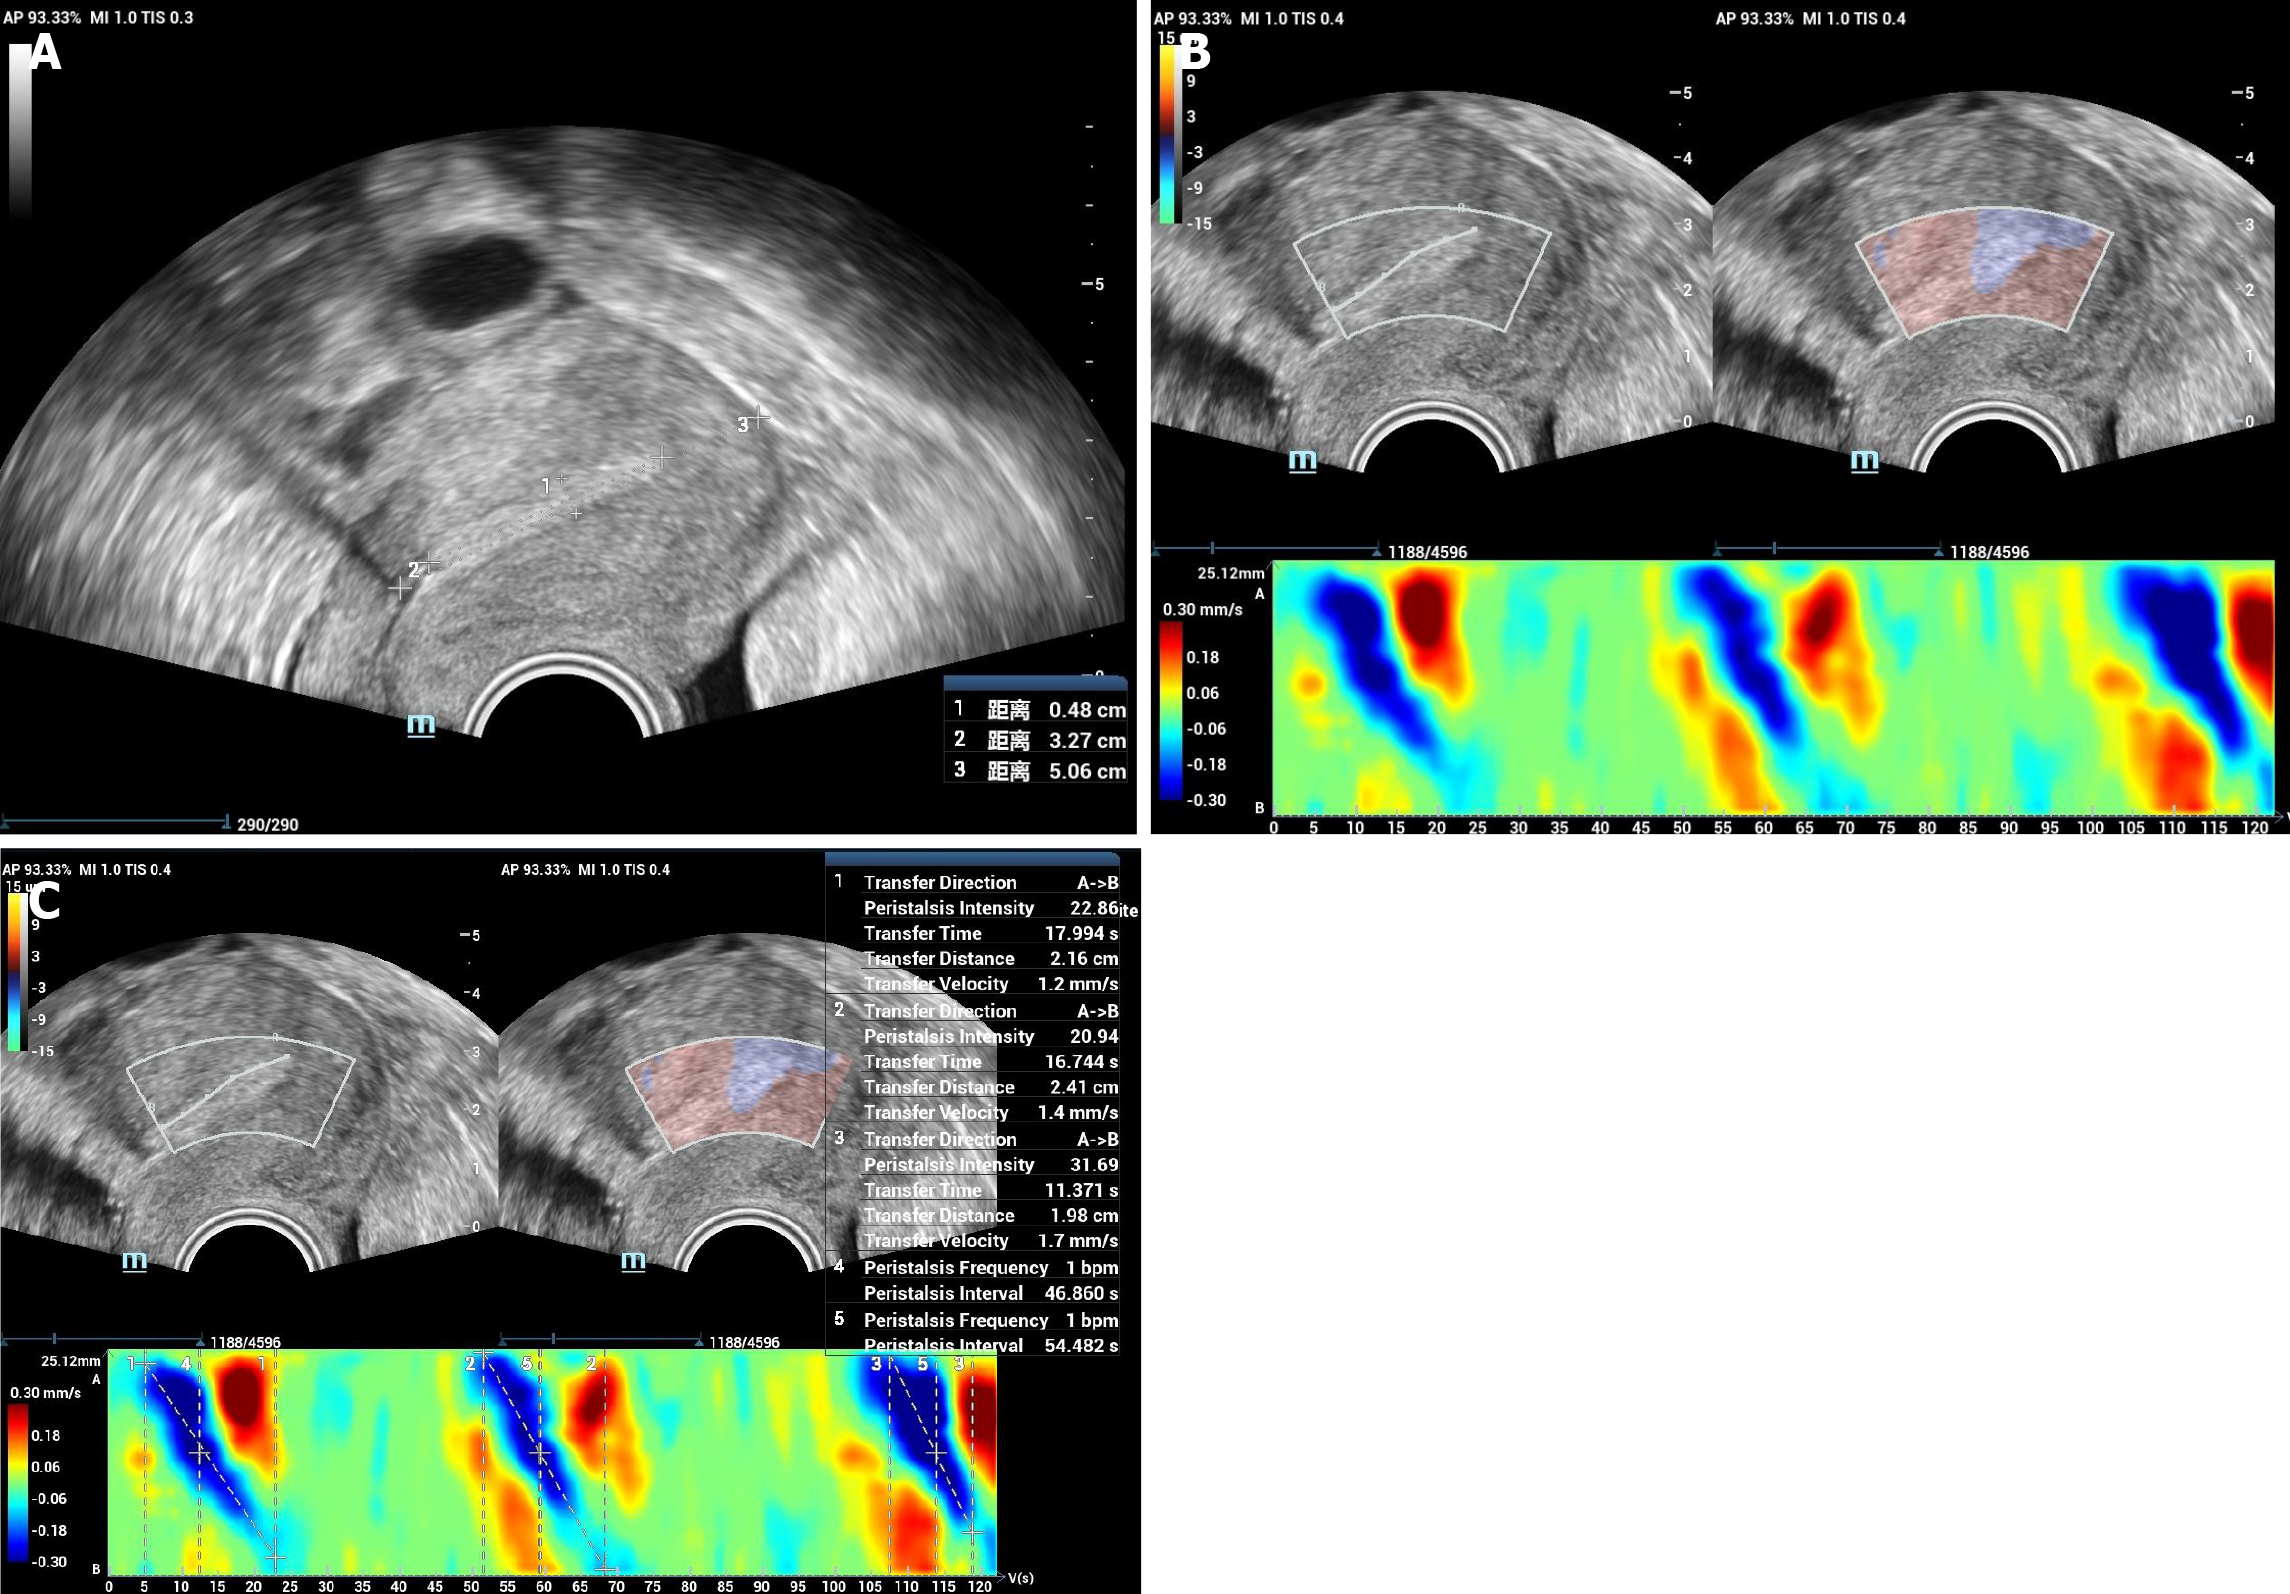

Figure 1 The color code image of endometrial peristalsis and the quantitative analysis.

A: Conventional ultrasound showed a normal uterus; B: Endometrial peristalsis analysis technique showed endometrial peristalsis with color code image; C: Quantitative analysis of figure B with quantitative parameters acquired including transfer direction, peristalsis intensity, transfer distance, transfer time, transfer velocity and peristalsis frequency.